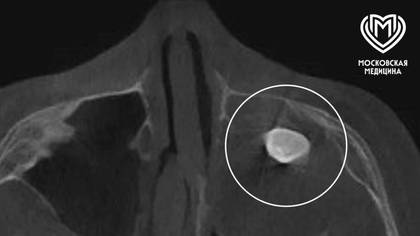

Хирурги Филатовской детской больницы Москвы удалили 15-летнему подростку зуб, который вырос в носу. Об этом во вторник, 17 марта, рассказали в столичном департаменте здравоохранения.

Мальчик обратился с жалобами на асимметрию лица и заложенность носа. Выяснилось, что в другой клинике у подростка в гайморовой пазухе нашли сформированный зуб, после чего предложили его удалить.

— Мальчику нужно было провести операцию по Колдуэллу-Люку. Сделав разрез, врачи обнаружили новообразование, внутри которого и находился зуб, — добавили в Telegram-канале ведомства.